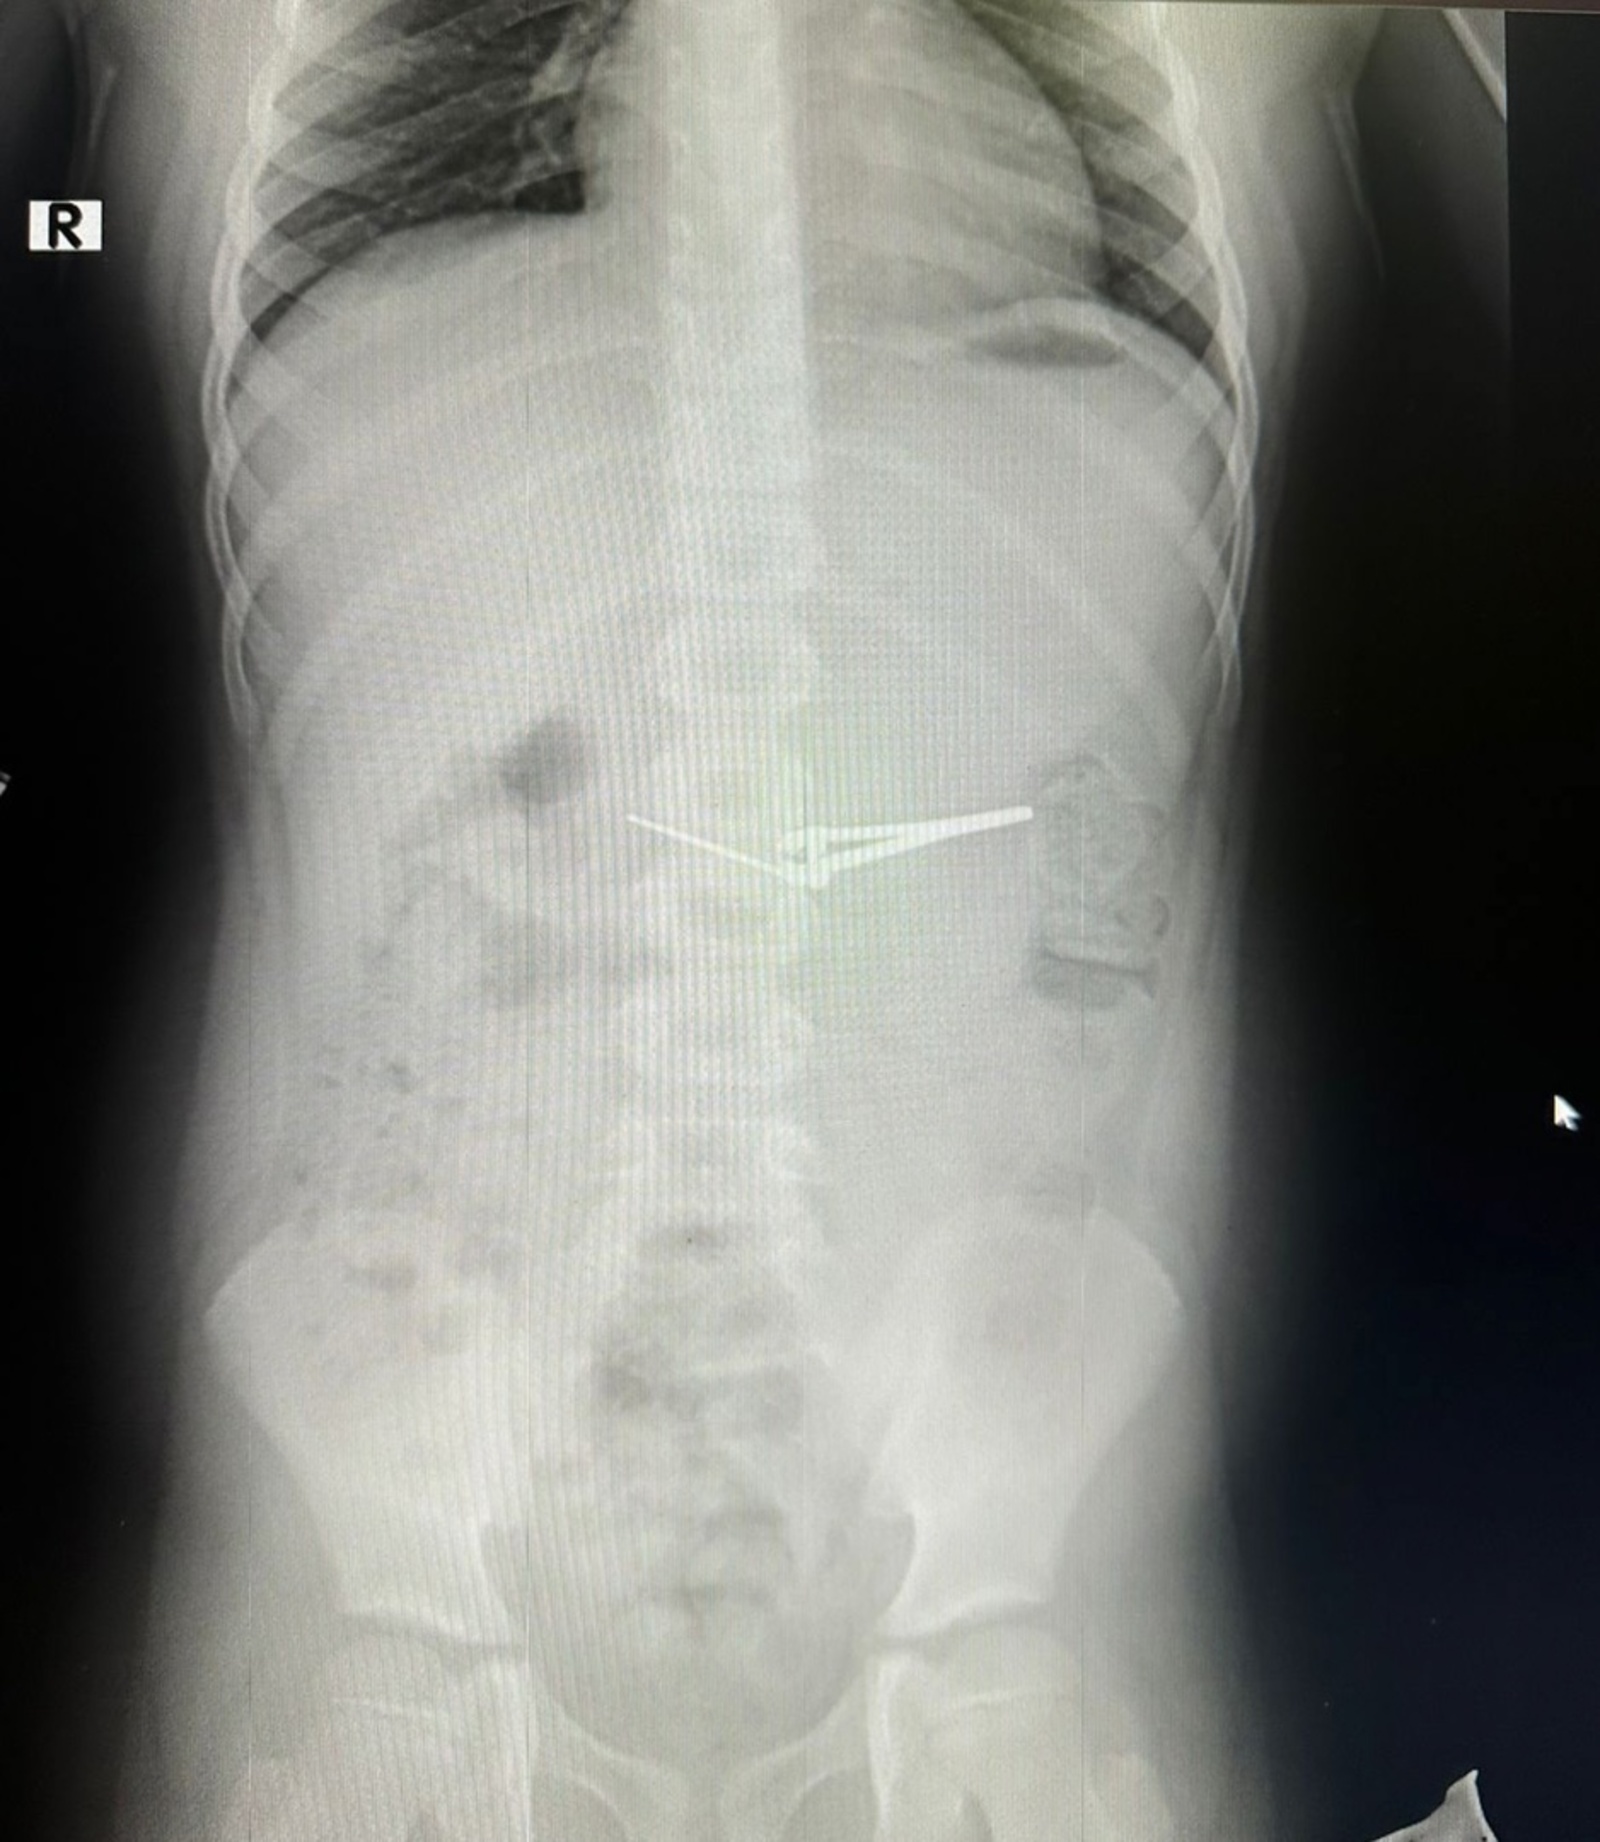

Врачи городской детской больницы № 17 в Уфе столкнулись с необычным медицинским случаем, когда шестилетний мальчик проглотил маникюрные щипцы. Этот инцидент вызвал серьезные опасения, и медики сразу же приняли меры для спасения ребенка.

Специалисты провели экстренную лечебную фиброгастроскопию, что позволило безопасно извлечь инородный предмет из желудка мальчика. Для этой процедуры была использована специальная корзина, которая помогает в таких сложных случаях.

Процедура проводилась под общим обезболиванием, что обеспечивало максимальный комфорт и безопасность для пациента. Врачи отметили, что хотя подобные случаи и редки, но требуют высокой квалификации и опыта от медицинского персонала.